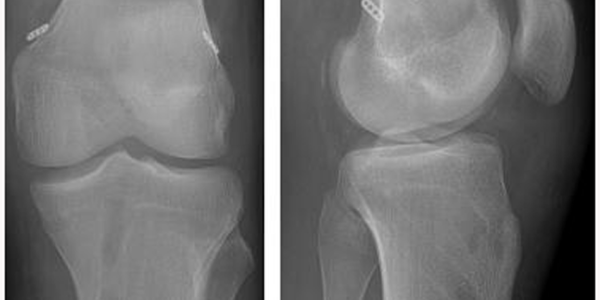

MPFL RECONSTRUCTION

The medial patellofemoral ligament is a part of the complex network of soft tissues that stabilize the knee.